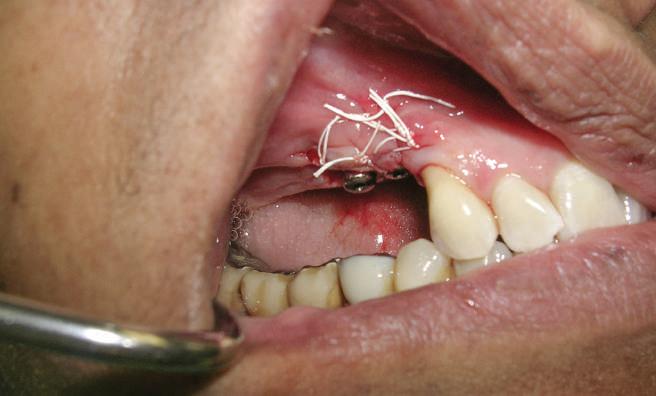

Reprepararea intraorală a bonturilor Acest pacient prezenta dentiţia maxilară compromisă, refuzând proteza mobilizabilă. Prin abordarea în etape, se menţin o parte din bonturile dentare naturale; s-a observat recesie în momentul amprentării pentru cel de-al doilea grup de implanturi.

Fig. 1 prezintă pacientul după inserarea primului set de bonturi implantare individualizate; dinţii naturali adiacenţi

sunt încă prezenţi pentru a susţine puntea provizorie.

Şapte luni mai târziu (fig. 2), acele bonturi individualizate din prima etapă au manifestat semne de recesie de 1-3mm. Atitudine: S-a decis reprepararea intraorală a tuturor bonturilor (fig. 3), astfel încât toate marginile bonturilor să fie la nivelul sau sub marginea gingivală (de notat că 1.1. şi 2.1. au fost submersaţi ulterior pentru a avea sprijin implantar deplin).

Deşi reprepararea a îmbunătăţit marcat estetica finală, a necesitat aplicarea şnurului de retracţie, amprente noi şi turnări noi.

Un caz separat dar similar ilustrează în figurile 4 și 5 reprepararea intraorală a bontului.

Cazul (1): Reprepararea intraorală a bonturilor Figurile

1. Aspect după inserarea primului set de bonturi implantare individualizate.

2. După 7 luni, bonturile individualizate din prima etapă au prezentat recesie de 1-3mm.

3. Bonturile repreparate intraoral.

Alt caz (1) Figurile

4. După osteointegrarea implantului 2.4., s-a observat recesia în etapa de amprentare a implantului 2.5.; s-a decis reprepararea marginilor bontului individualizat CAD/CAM 2.4. Înainte de preparare s-a aplicat şnur de retracţie pentru a evita lezarea ţesutului şi a îmbunătăţi vizibilitatea dintelui 2.3. şi a marginii bontului implantar individualizat. Aşa cum era de aşteptat, recesia a fost mai mare de-a lungul versantului distal al bontului 2.4. adiacent locului de extracţie vindecat/cu implantul mai nou.

5. Bontul individualizat aplicat (2.5.) cu bontul repreparat anterior (2.4.). Nu a survenit recesie nouă de o perioadă de peste 3 ani.